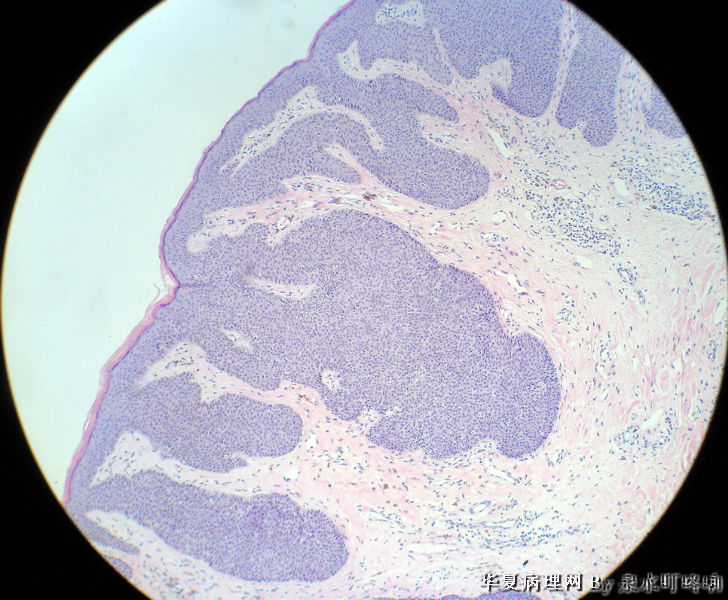

男,80岁,左耳后肿物十余年。

参考诊断

棘层肥厚型脂溢性角化症